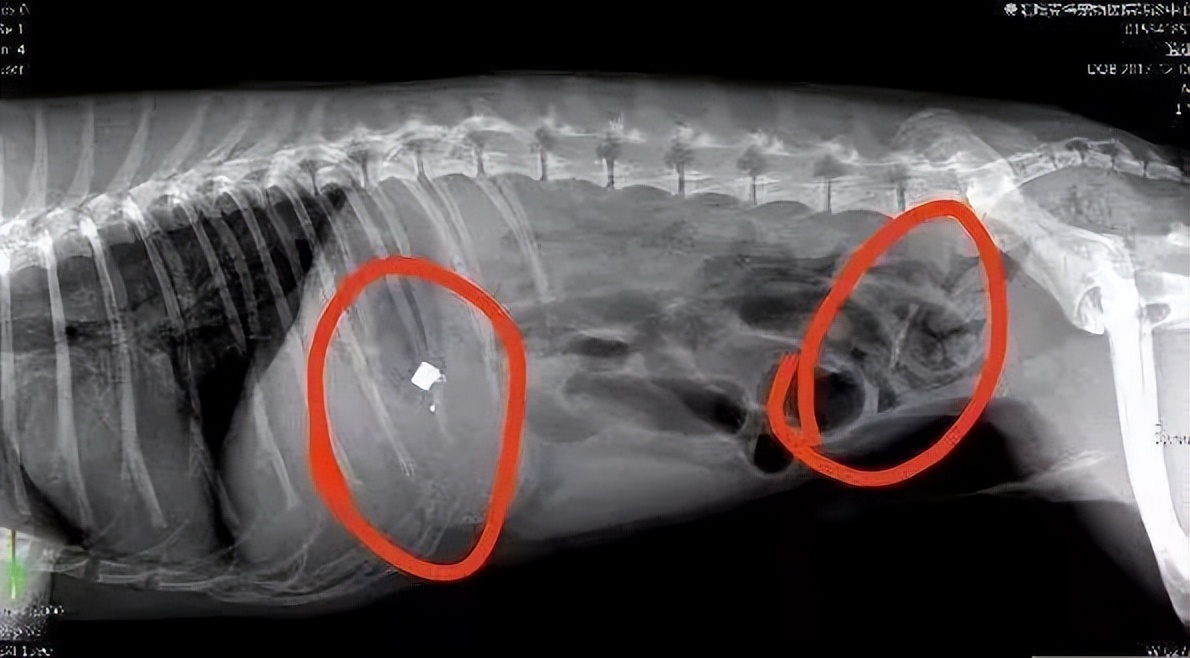

如果铲屎官发现猫咪有以上症状,并且铲屎官在抚摸猫咪腹部的时候能够接触到硬物,就可以怀疑猫咪是不是吞了异物了,建议及时带猫咪去医院拍X光来确诊。

如果猫咪误食的异物过大,或者误食了一些比较尖锐不容易突出的物品,单靠催吐是无法解决的,那么铲屎官只能尽快带猫咪去医院医院进行拍片,然后手术了。